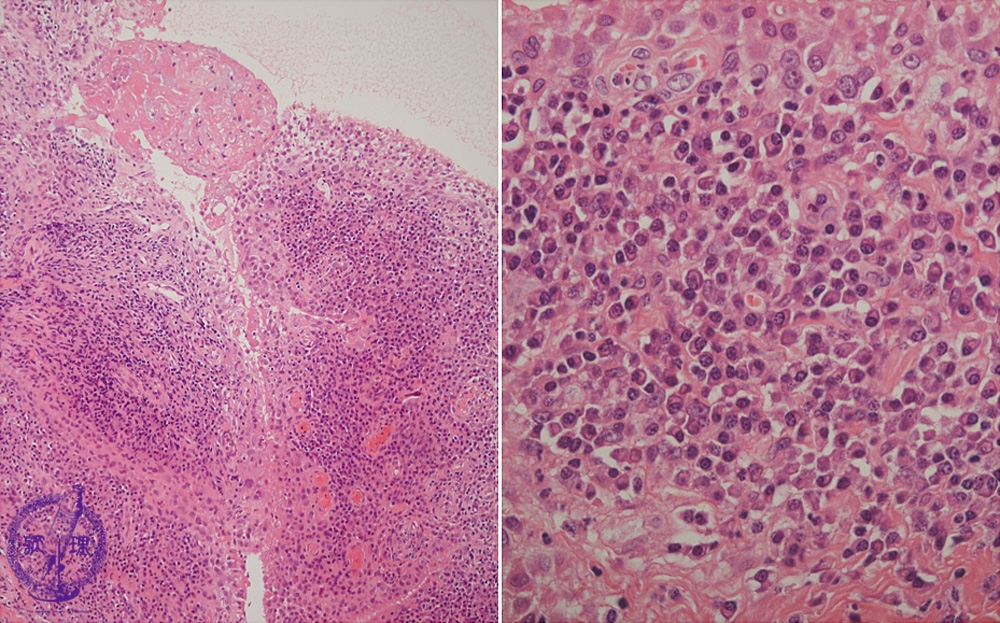

Microscopic view (HE; left-middle power view, right-high power view): Proliferation of stratified synovial cells and fibrin deposits on the surface. Among inflammatory cells, plasma cells are prominent.